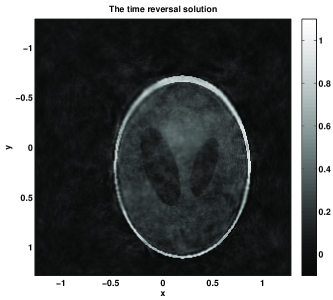

Figure 4: T=4T0𝑇4subscript𝑇0T=4T_{0}. The time T𝑇T is doubled, and it is greater than T1subscript𝑇1T_{1}. The error of the NS solution is 4.99%percent4.994.99\% with k=8𝑘8k=8 (999 terms) of the series vs. error 7.07%percent7.077.07\% for the TR one. The TR reconstruction gets better as expected. While the singularities are recovered correctly, the low frequency part in the TR reconstruction is still not well recovered as evidenced in the slice diagrams. For example, in Figure 4(e)(g) for the TR reconstruction there are oscillations in some flat regions; in contrast, in Figure 4(f)(h) for the NS reconstruction those oscillations are gone in the same flat regions.

Figure 4: Example 1 with the non-trapping speed c1subscript𝑐1c_{1}. Case 2: T=4T0𝑇4subscript𝑇0T=4T_{0}. (a): the boundary distance map. (b): the exact initial condition. (c): the time reversal solution. (d): the Neumann series solution. (e): x𝑥x-slices of the time reversal solution (continuous line) and the exact solution (a dashed line). (f): x𝑥x-slices of the Neumann series solution (continuous line) and the exact solution (a dashed line). (g): y𝑦y-slices of the time reversal solution (continuous line) and the exact solution (a dashed line). (h): y𝑦y-slices of the Neumann series solution (continuous line) and the exact solution (a dashed line).